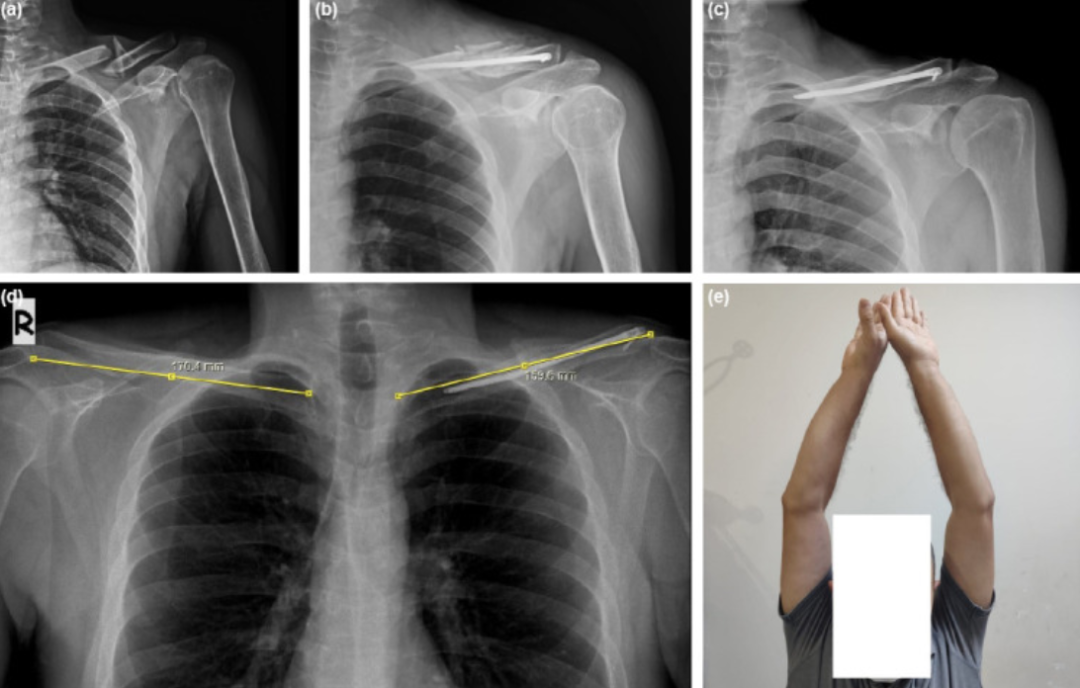

髓内钉固定改良版(锁骨中段骨折)

1、交锁髓内钉固定

半沙滩椅位,从骨折线外侧切开一个5-7cm切口,显露骨折线后扩髓。使用t型手柄,通过后外侧孔旋转插入直径最大且长度合适的钉子。用2.5 mm的钻头将导杆固定在钉的外侧锁孔上。

(a, b)一名38岁男性左侧锁骨粉碎性骨折术前及术后8周前后位X光片;(c, d)术后2年骨折愈合后前后位X光片,显示创伤后短缩6.3%;(e)同一患者的临床图像。